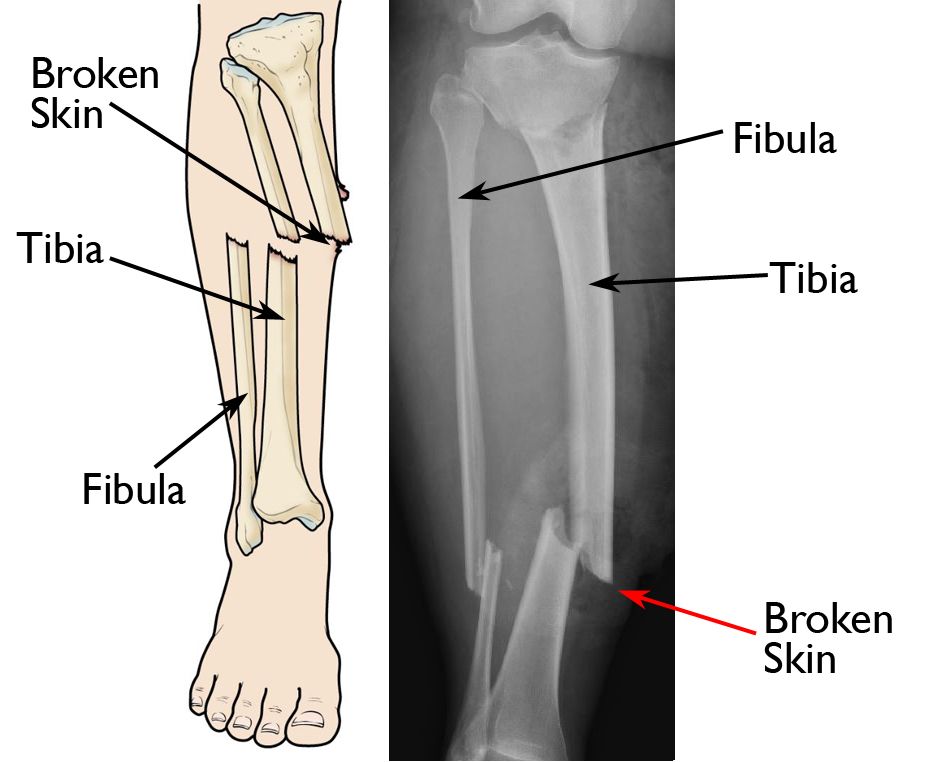

Partial articular, split fracture these fractures of the distal tibia are usually caused by low energy traumas with rotational or pure bending forces. Type a2 injuries are vertebral body fractures in which the fracture involves both endplates. This fracture type is subdivided: Split fractures of the femoral head are classified by ao/ota as 31c1. These fractures involve the articular surface. A fracture is a broken bone, the same as a crack or a break. A break of any size is called a fracture. If more pressure is put on a bone than it can stand, it will split or break. In some cases, it is difficult or even impossible to. If the broken bone punctures the skin, it.

Split Fracture Definition . Partial articular, split fracture these fractures of the distal tibia are usually caused by low energy traumas with rotational or pure bending forces. This fracture type is subdivided: These fractures involve the articular surface. Type a2 injuries are vertebral body fractures in which the fracture involves both endplates. A fracture is a broken bone, the same as a crack or a break. If more pressure is put on a bone than it can stand, it will split or break. A bone may be completely fractured or partially fractured in any number of ways (crosswise, lengthwise, in multiple pieces). Split fractures of the femoral head are classified by ao/ota as 31c1. Pincer or split fractures are coronally oriented vertebral body fractures that involve the superior and inferior vertebral body endplates but do not. In some cases, it is difficult or even impossible to. The prognosis depends on whether the fracture involves the lateral or the medial articular surface. A break of any size is called a fracture. Partial articular fractures with a condylar split are classified by the ao/ota as 41b1 fractures. If the broken bone punctures the skin, it.